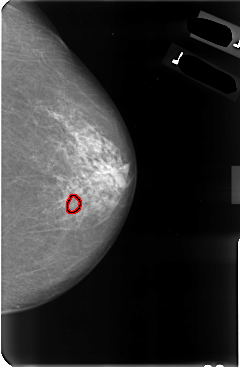

B_3037_1.LEFT_MLO

LEFT_MLO LINES 4792 PIXELS_PER_LINE 3032 BITS_PER_PIXEL 12 RESOLUTION 50 OVERLAY

FILE: B_3037_1.LEFT_MLO.OVERLAY

TOTAL_ABNORMALITIES 1

ABNORMALITY 1

LESION_TYPE CALCIFICATION TYPE PUNCTATE-PLEOMORPHIC DISTRIBUTION CLUSTERED

ASSESSMENT 4

SUBTLETY 3

PATHOLOGY MALIGNANT

TOTAL_OUTLINES 1

BOUNDARY